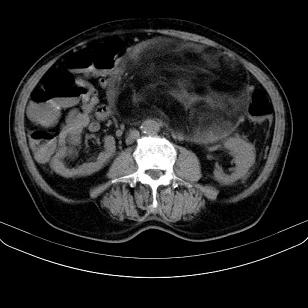

标题: CT21671:男,88岁,左上腹包块 [打印本页]

标题: CT21671:男,88岁,左上腹包块

患者因咳嗽而住院,自觉右上腹包块,无其他不适。

腹膜后高分化脂肪肉瘤

腹膜生占位性病变,脂肪肉瘤可能。

另肠腔扩张及液平,肠梗阻?